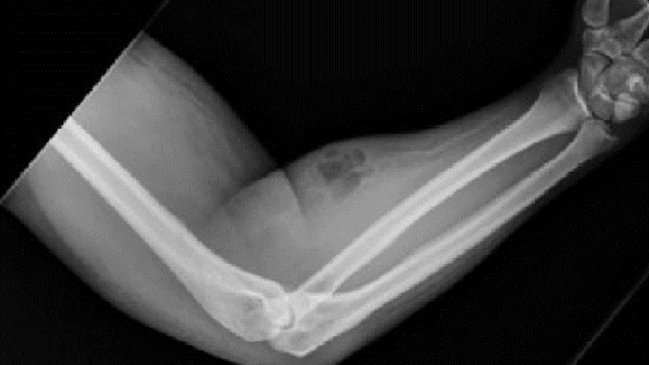

Un rarísimo caso quedó al descubierto gracias a la revista médica Irish Journal: El de un hombre de 33 años que solía inyectarse su propio semen en el brazo para tratar sus dolores crónicos en la espalda.

Su brazo estaba evidentemente inflamado, pues se inyectaba al menos una vez al mes durante los últimos 18 meses.

El dolor de su espalda comenzó cuando un año y medio antes levantó un objeto pesado. Allí decidió aplicarse tres dosis.